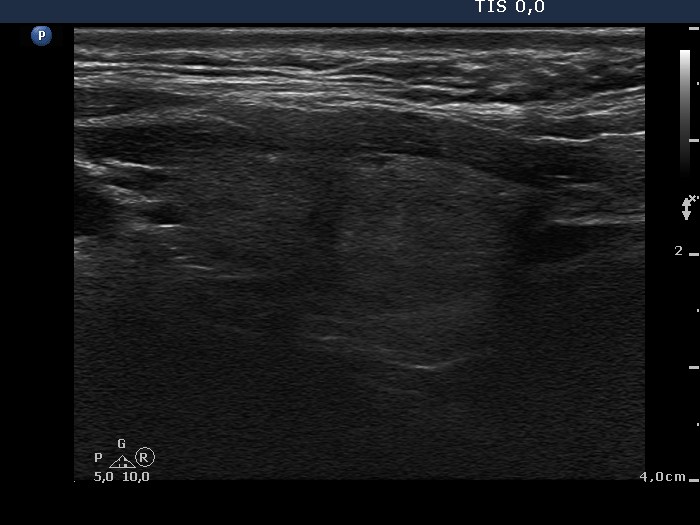

100 consecutive cases of papillary cancer - case 016 (ultrasonographic picture 8)

Left lobe, longitudinal scan.